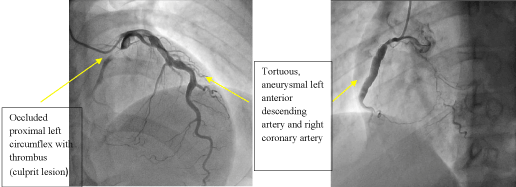

Trans-radial coronary angiogram revealed tortuous and aneurysmal dilatation (ectatic vessels) of all three major coronary arteries (Figure 3a, 3b) with huge thrombus in the proximal segment of left circumflex (LCx) artery, the culprit lesion was identified. Left coronary system was engaged with XB 3.0 6-French guiding catheter through right radial access with 6F sheath. The lesion was crossed by Run through NS floppy (Terumo) hydrophilic 0.014 inches wire. Among different strategies to deal with huge thrombus burden such as Plain Old Balloon Angioplasty (POBA), thrombus aspiration and intracoronary glycoprotein IIb/IIIa inhibitor, we proceeded with thrombus aspiration. Thrombuster II (Kaneka Corporation) thrombus aspiration catheter introduced into the target vessel and suctioning performed. Blood clots aspirated as shown (Figure 4). After few aspirations, failed to do further suctioning and planned to flush as the catheter may get blocked from aspirated thrombus. Some degree of resistance was felt while removing the catheter from the vessel. The thrombus aspiration catheter finally came out with slight pulling force but noted that the tip was missing (Figure 5). Angiographically, the tip of Thrombuster II catheter seen attached to the guidewire (Figure 6). The guidewire can move freely along the mid and distal LCx but failed to withdrawal at the proximal LCx area.

Figure 3a. Left coronary artery Figure 3b. Right coronary artery